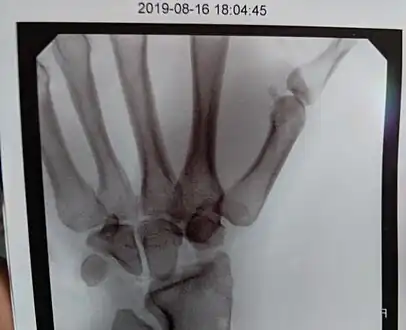

Negative ulnar variance. -

Left hand x-ray with Kienbock's Disease showing 4 mm negative ulnar variance and Kienbock's Disease Stage IIIB -

Left hand x-ray with Kienbock's Disease -